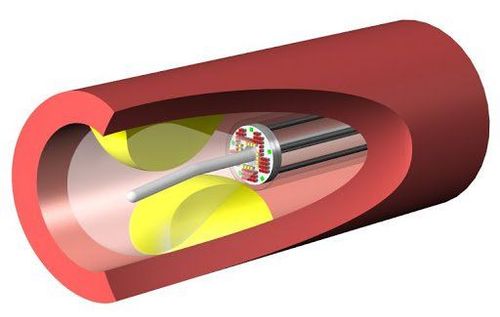

Siêu âm trong lòng mạch là kỹ thuật siêu âm sử dụng ống thông đặc biệt nhằm quan sát, đánh giá hình ảnh cấu trúc mạch máu. Một đầu của ống thông được gắn vào đầu dò phát sóng siêu âm, đầu còn lại được kết nối với hệ thống máy ghi nhận và xử lý hình ảnh. Ống thông sẽ được luồn qua một dây dẫn thẳng vào trong lòng mạch máu, đến vị trí cần khảo sát và ghi lại hình ảnh mạch máu. Thông qua hình ảnh thu được, các bác sĩ sẽ đánh giá tình trạng mạch máu và chẩn đoán các bệnh lý liên quan.

Ống thông IVUS là một ống mỏng. Một đầu của ống gắn vào đầu dò siêu âm, đầu còn lại kết nối với máy tính để truyền tín hiệu từ đầu dò thành hình ảnh trên màn hình. Siêu âm trong lòng mạch giống các kỹ thuật siêu âm khác, cũng sử dụng sóng âm thanh tần số cao để ghi lại hình ảnh cấu trúc mạch máu.

Tùy từng tình trạng cụ thể mà một số bệnh nhân có thể sẽ được chỉ định gây mê toàn thân, còn lại bệnh nhân sẽ được gây tê tại chỗ. Bác sĩ sẽ sát khuẩn vị trí đặt ống thông và phủ vải phẫu thuật lên trên. Một dụng cụ dẫn đường sẽ được bác sĩ luồn vào động mạch cẳng tay hoặc động mạch đùi. Ống thông được luồn vào dụng cụ dẫn đường, đi đến vị trí cần khảo sát trên một sợi dây dẫn mềm. Quá trình này được thực hiện dưới hướng dẫn của màn tăng sáng. Tại đây, sóng siêu âm sẽ tạo ra hình ảnh của cấu trúc mạch máu, phản xạ lại màn hình hiển thị.